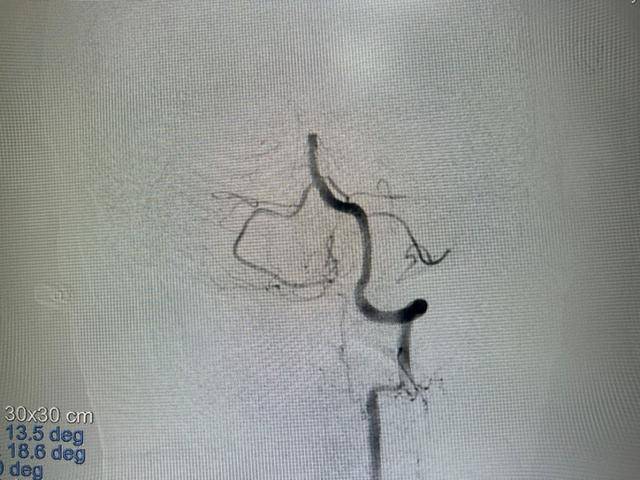

大众卫生报·新湖南客户端5月16日讯(通讯员 黄昊)62岁的李大叔有多年房颤却未重视,近日突然昏迷倒地,被紧急送往湖南省第二人民医院。刚进急诊,他的瞳孔已大小不一,呼吸微弱,血氧饱和度不稳定,医生火速